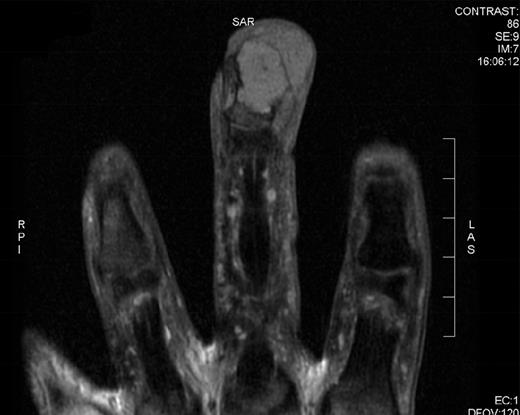

Clinically a differential diagnosis of an aggressive adenocarcinoma was suspected, but this was not supported by multiple radiological investigations. CT and MRI of the lesion showed a vascular destructive lesion that was causing severe erosion of the distal interphalangeal bone (Figs 1 and 2, respectively). A plain chest radiograph at that time showed no pulmonary metastasis.

MRI of the right middle finger showing a vascularly destructive space occupying lesion 23 × 15 × 20 mm in size. The mass was multiloculated and causing severe erosion of distal interphalangeal bone. There lesion was iso-intense on T1 weighting, homogenously hypo-intense on STIR sequences and showed intense homogenous enhancement on post gadolinium fat sat T1 sequences.